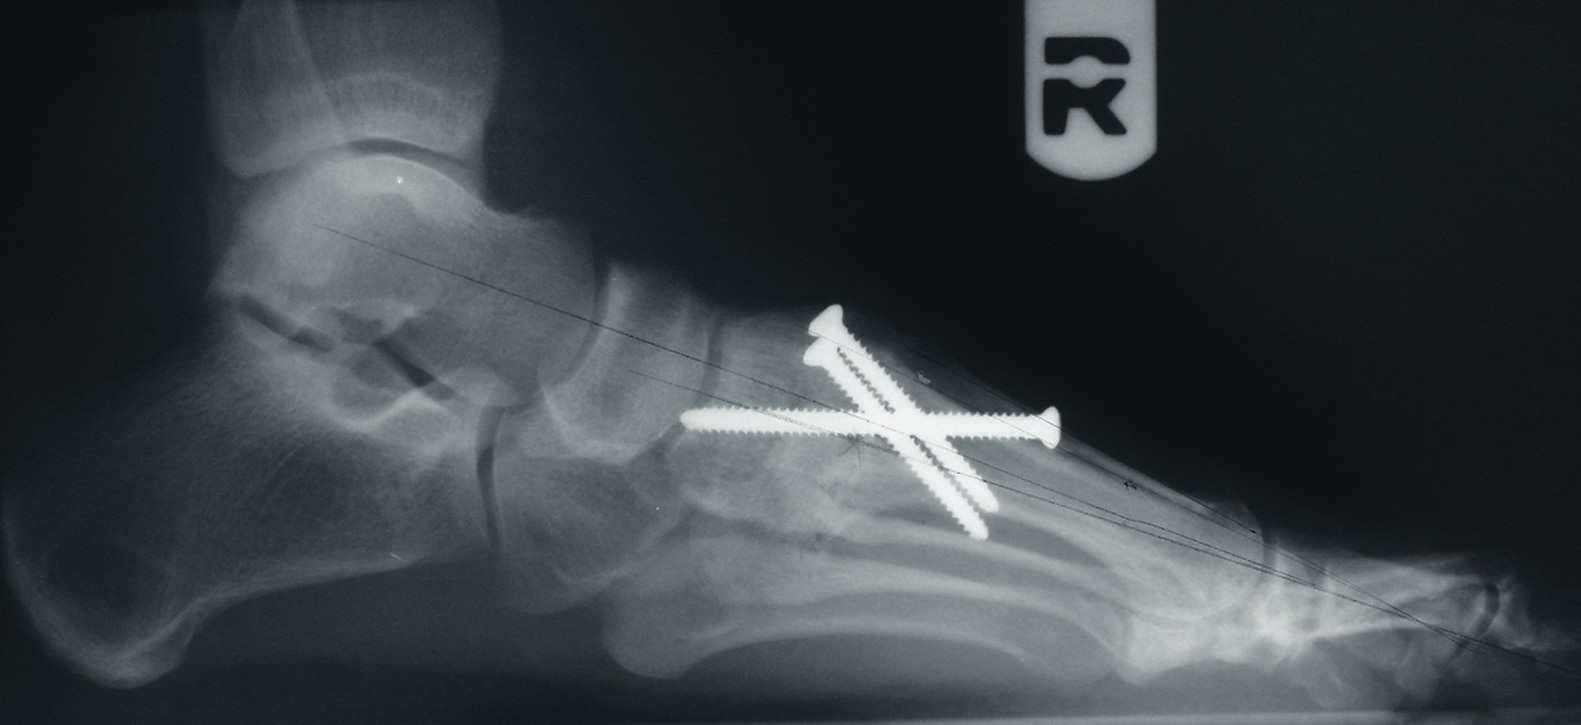

One should place the patient into a supine position and utilize a tourniquet. Evaluate post-anesthesia assessment of the first MPJ range of motion. Manually distract the first MPJ and plantarflex the first metatarsal. Dorsiflex the hallux to determine the obtainable first MPJ range of motion and evaluate for crepitus. If there is first ray hypermobility and no crepitus, one may be able to salvage the first MPJ by translating the first ray plantarly and stabilizing the medial column. Initially, surgeons should address contributing global pathology. Then proceed to the first ray and make a dorsomedial skin incision spanning the first MPJ. Retract the neurovascular structures. Make a longitudinal incision to bone, spanning the distal one-third of the first metatarsal and proximal one-half of the proximal phalanx. Evaluate the adjacent cartilage and make a critical decision to preserve or destroy the joint. It is important to realize that evaluation of cartilage quantity and quality via direct intraoperative visualization weighs heavily upon the final decision to perform a joint preservation or destructive procedure. One should strongly consider joint destructive procedures if greater than 30 percent of the dorsal portion of the first metatarsal head presents as grade III to grade IV chrondromalacia. One must independently evaluate grade III and IV chrondromalacia and osteochondral defects in the remaining 70 percent of the metatarsal head. Small cartilage lesions may yield themselves to debridement, drilling or OATS procedures whereas large cartilage defects will likely result in arthrodesis. If the joint is salvageable and one identifies first metatarsocuneiform hypermobility, perform a cheilectomy and a subsequent, sagittal Lapidus procedure. If one identifies hypermobility or posttraumatic first metatarsal angular pathology, correct it after completing the first MPJ soft tissue and osteophyte debridement. If one decides to perform arthrodesis on the joint, debride identified osteophytes, loose bodies, synovitis and scar tissue. Denude the adjacent cartilaginous surfaces to the healthy level of bleeding bone via curettage or via convex distal and concave proximal reamers. Fenestrate the adjacent bone surfaces with a 1.0- or 1.5-mm drill bit. Temporarily fixate the hallux by utilizing two K-wires in the desired position. The position should be approximately 20 to 30 degrees dorsiflexed in relation to the first metatarsal declination; abducted and parallel to the second digit; and with the nail void of frontal plane varus or valgus rotation. Obtain an AP radiograph to evaluate the bony apposition and alignment of the proposed first MPJ arthrodesis. Also obtain a lateral radiograph with the foot loaded in order to evaluate the hallux and its relationship to the first ray. After obtaining the desired position, utilize two fully threaded (3.5 or 4.0) crossing cortical screws for permanent fixation. Place the first screw from proximal medial to distal lateral and place the second screw from distal medial to proximal lateral across the first MPJ. Ensure the screws do not cross at the level of the joint. Use a 3.5-mm burr to create a dell in the cortical bone where the head of the screws engage the bone as Manloli and Hansen have described.48 After obtaining rigid internal fixation across the first MPJ, utilize a shear strain autograft (harvested via a percutaneous calcaneal grafting technique) at the arthrodesis site.57 Place the autograft in two troughs created by the 3.5-mm burr at the arthrodesis site. Use a bone mallet and tamp to provide a press fit.58